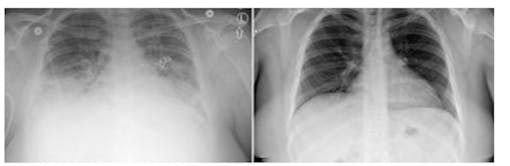

But by day two, all the phytol rats had died or were suffering so badly—gasping, unresponsive—that lab scientists euthanized them. Directors halted the phytol arm of the trial. The PG rats finished their 14 days of exposure and all survived, with no lasting effects.

Among the findings from phytol-exposed rat autopsies:

- There was “acute toxicity in all dose groups.”

- Phytol caused “severely purple” lungs that were “hemorrhaging.”

- The rats’ nose, throat, and lung tissue had melted away in a process called necrosis.